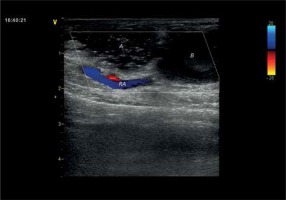

Figure 4

Communication between the first and second chamber with a flow characteristics

A – first chamber, B – second chamber.